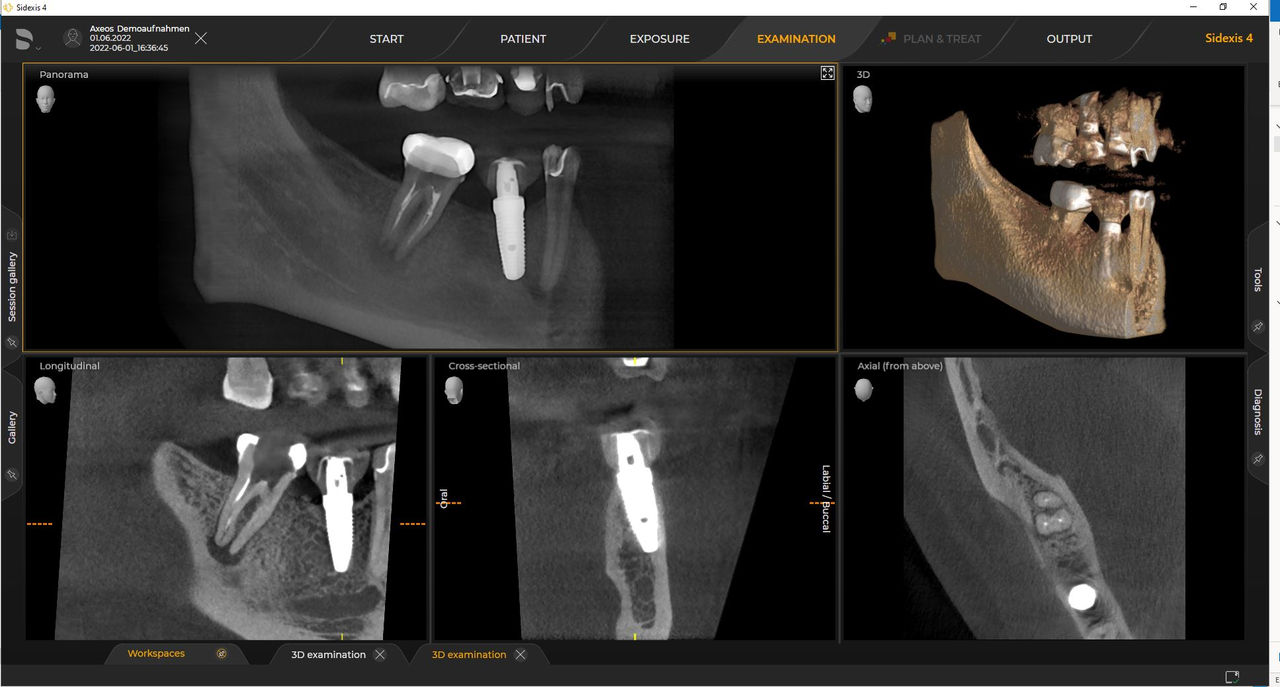

Los requisitos siguen aquellos del software de procesamiento de imágenes de Sidexis 4 y Axeos. Para obtener más detalles, consulte los requisitos del sistema Sidexis 4 y los requisitos de instalación de Axeos.

Las unidades 3D de Dentsply Sirona funcionan exclusivamente con Sidexis 4. Sin embargo, la migración de datos de Sidexis XG a Sidexis 4 es muy fácil. Sidexis 4 permite una experiencia digital completa con las últimas herramientas.